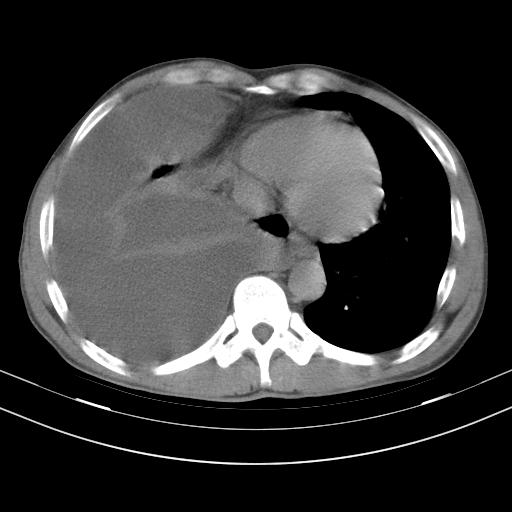

男性,44岁,结核病史多年。现胸闷气短,咳嗽,偶咳血。

右侧胸腔积液

右肺下叶不张

双肺多发结节影最分空洞形成考虑占位不除外结核

双肺陈旧性病变

1、右侧大量胸腔积液伴右肺压缩性膨胀不全,建议抽液治疗后复查 2、两肺继发性tb伴空洞形成。

1)两肺继发性肺结核伴空洞形成,左肺多发性结核球。2)右侧大量胸腔积液伴右肺部分膨胀不全。3)纵隔淋巴结肿大。